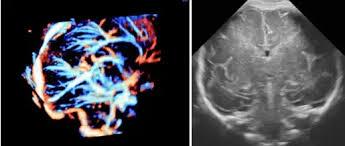

Fetal Neurosonography test service in Sonipat | Fetal India

(Sonipat, Delhi) Elevate your prenatal care with Fetal India's advanced Fetal Neurosonography services. Unmatched in accuracy and resolution, our imaging techniques offer a comprehensive view of your baby's develop...